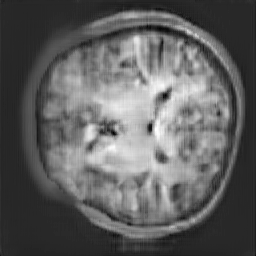

The study utilizes three 3D datasets, namely the GSP dataset[3], the LIDC-IDRI dataset[1], and the dataset employed for the Lung Nodule Analysis 2016 (LUNA16) challenge[21] which is a subset of LIDC-IDRI dataset. Samples from generated images at different stages of training are presented in Fig. 2 and Fig.3.

Figure 2: Synthetic images of CRF-GAN and HA-GAN at different iterations of training on GSP dataset